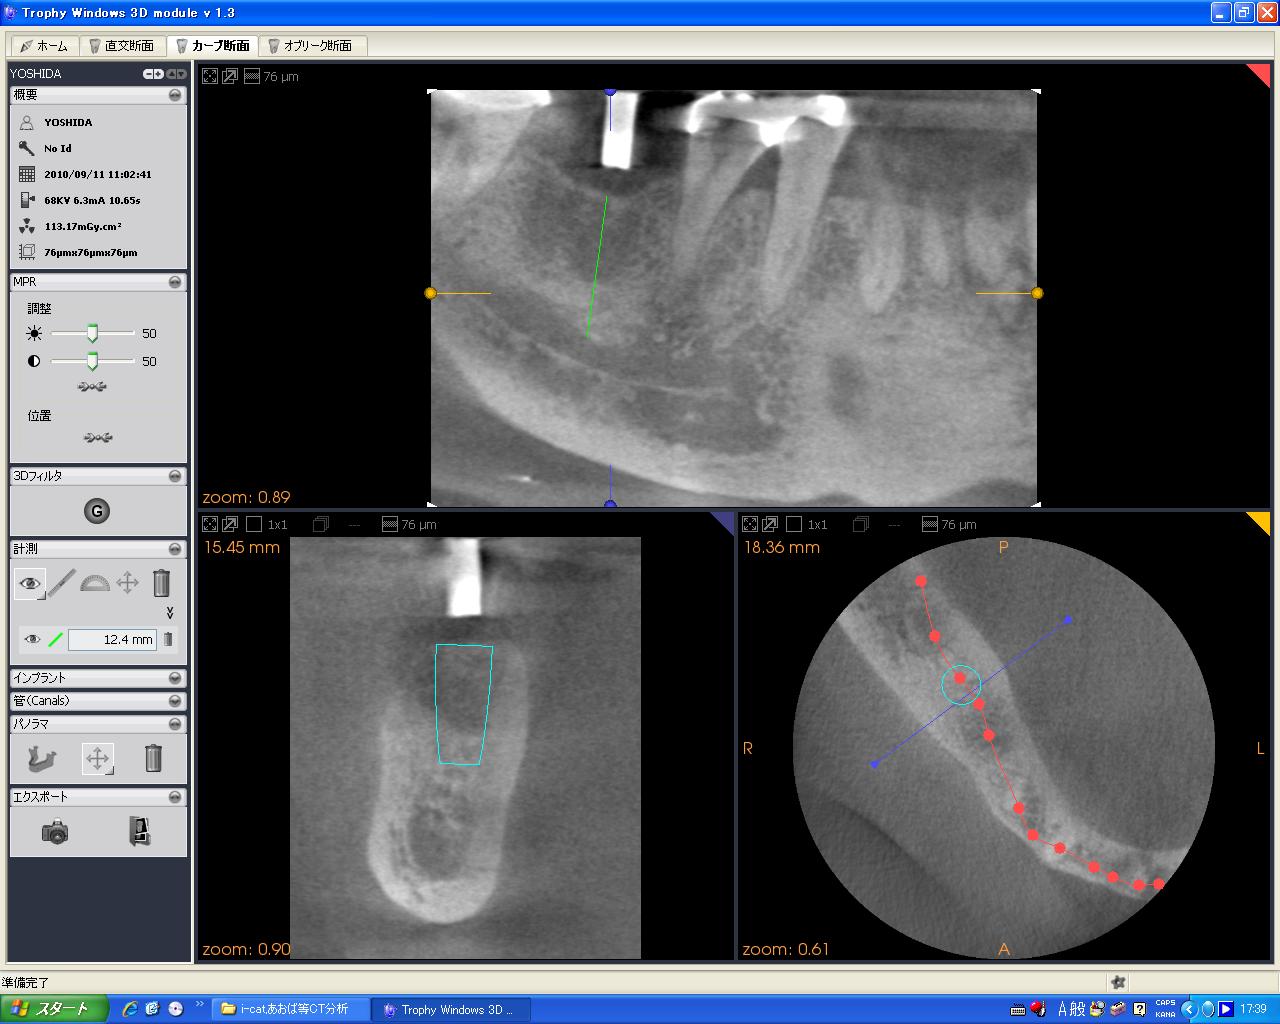

2017年4月 CT導入に伴い、全ての術前検査を当院で行えるようになりました。

まず外科手術でフィクスチャーと呼ばれる人工歯根を埋入します。このときCTなどを用いて綿密な治療計画を立てるため、安全に狙った位置へ埋入することができます。

CT(3DX)撮影+分析(同部位1~3本程度) ¥15,000